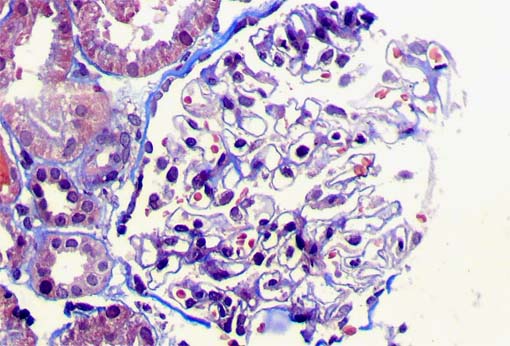

Figure 2.

Masson's trichrome stain,

X400.